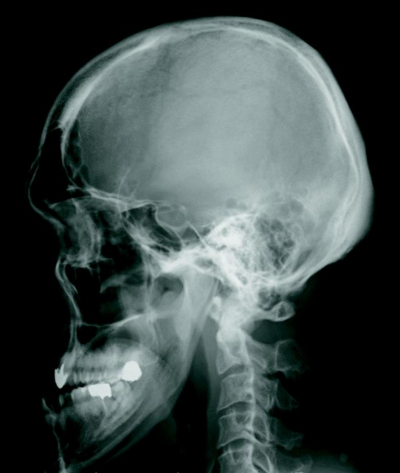

内分泌検査所見:GH 8.5 ng/mL(男性の基準 2.5以下)、IGF-1 780 ng/mL(34歳男性の基準 102〜283)、ACTH 35 pg/mL(基準 7.2〜63.3)、プロラクチン 62.0 ng/mL(基準 3.6〜12.8)、コルチゾール 14 μg/dL(基準 6.24〜18.0)。頭部単純エックス線写真を別に示す。